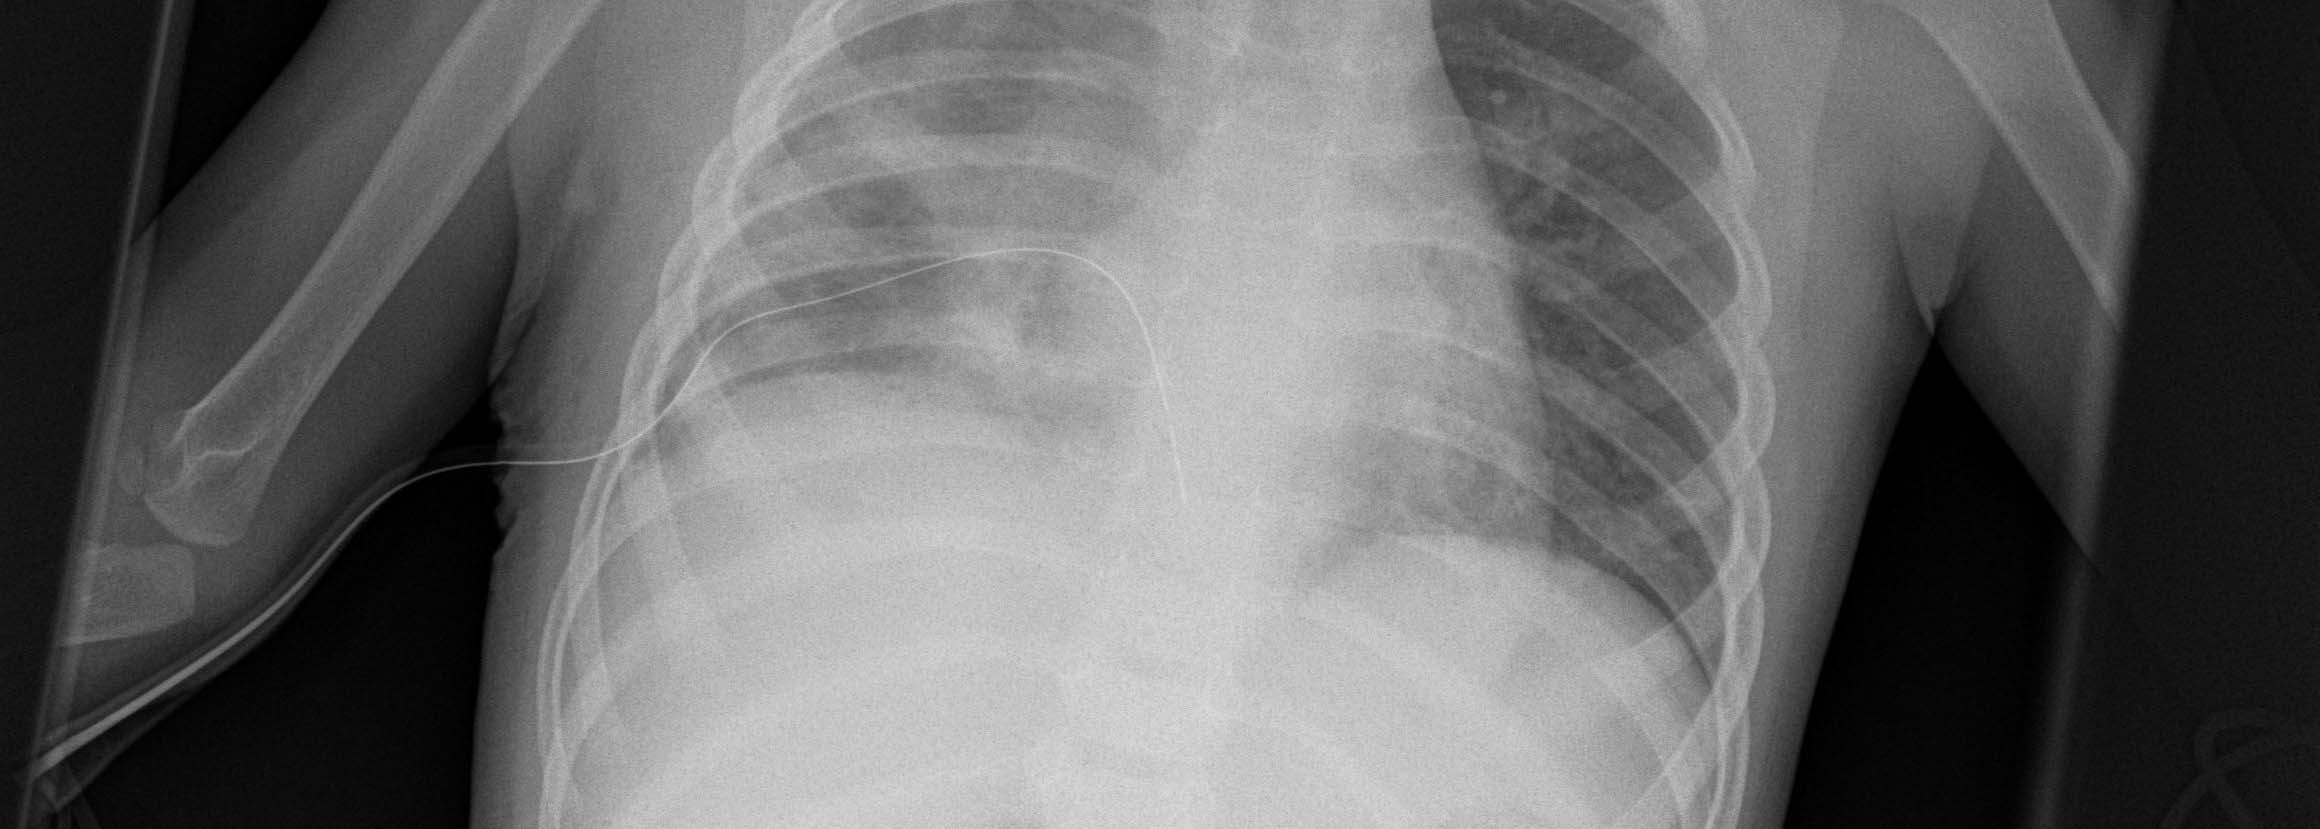

Thoracic Surgery in Children

Together with the specialists in pediatric surgery and the pediatric clinic, we attend to children with thoracic diseases and perform thoracic surgery when appropriate after thorough examination and analysis of the disease. All thoracic surgical procedures including minimally invasive keyhole surgery are used here. Our little patients benefit from the vast experience of many specialists from a wide variety of medical disciplines who specialize in the treatment of children.